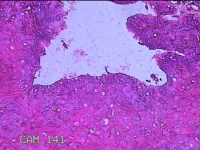

宫颈12点处活检

性别

女

年龄

42岁

临床诊断

人乳头瘤病毒感染

一般病史

发现人乳头瘤病毒感染一个月。

标本名称

大体所见

灰白粉红色不规则碎组织0.7x0.5x0.2cm一堆。